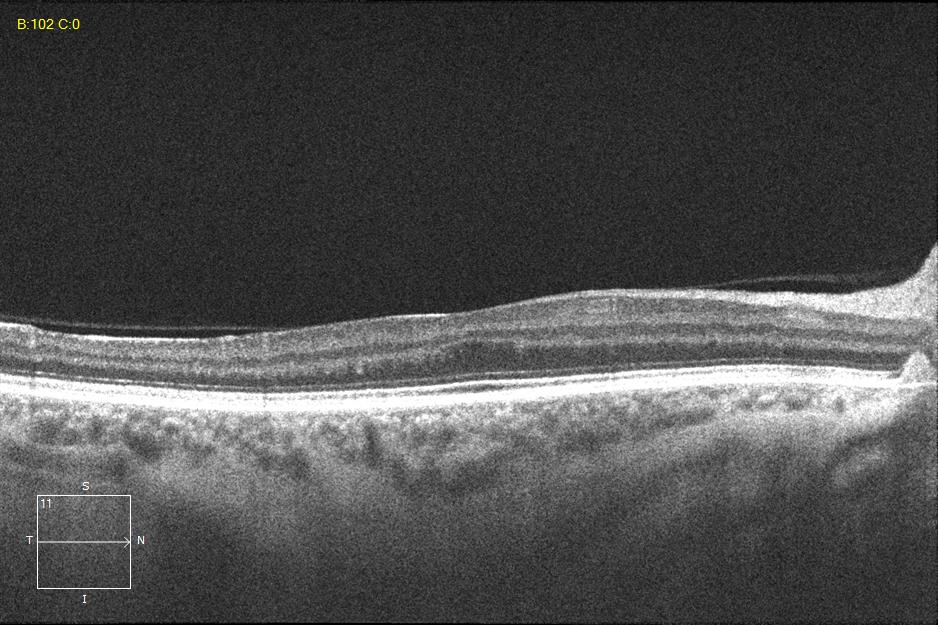

Two different patients with isolated foveal hypoplasia grade 2. The definitions of fovea plana and foveal hypoplasia have led to controversy among experts. The term fovea plane refers to the anatomical absence of a foveal pit. An estimated 3% of children with clinically normal eyes have an underdeveloped foveal pit on OCT. According to some experts, a foveal pit is not absolutely necessary for foveal cone specialization. A diagnosis of fovea plana alone does not automatically herald functional disability. It is possible to maintain adequate visual acuity in an eye with a fovea plana. Foveal hypoplasia refers to an underdeveloped fovea with vision loss. Foveal hypoplasia has also been seen in conditions such as aniridia, albinism, achromatopsia, nanophthalmus, and incontinence. pigment and premature retinopathy.

In contrast to other definitions, Thomas et al. defined foveal hypoplasia as the persistence of inner retinal layers in the fovea and developed a grading system based on optical coherence tomography features. According to this grading system, grades 2, 3, and 4 of foveal hypoplasia corresponded to the fovea plana.

Leicester Grading System for Foveal Hypoplasia;

Grade 1a foveal hypoplasia is associated with an almost normal pit resembling a “V” shape and outer segment (OS) elongation and outer nuclear layer (ONL) expansion relative to parafoveal OS and ONL lengths, respectively.

Grade 1b foveal hypoplasia is associated with a shallow indentation and OS prolongation and ONL widening relative to parafoveal OS and ONL lengths, respectively.

Grade 2 foveal hypoplasia has all the features of grade 1, except that there is no pit.

Grade 3 foveal hypoplasia represents all the features of grade 2 except that there is no lengthening of the OS segment.

Grade 4 foveal hypoplasia represents grade 3, except that ONL expansion is not present in the fovea (called the fovea plana).

Atypical foveal hypoplasia is characterized by distortion of the inner segment ellipsoid band, creating a shallow foveal pit and a hyporeflective zone.